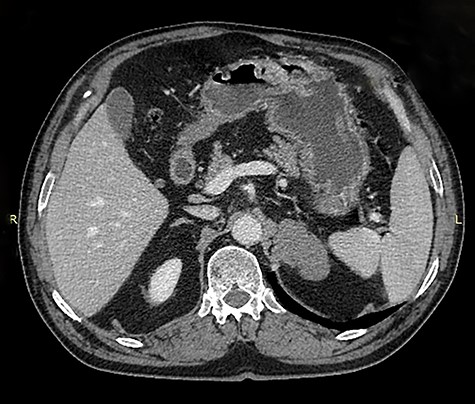

An asymptomatic 75-year-old Caucasian male was referred to our institution for the evaluation of an incidental left adrenal mass pointed out on computed tomography (CT) scan at medical checkup. The patient had a past medical history of hypertension and benign prostatic hyperplasia. The medication list included perindopril, indapamide, bisoprolol and tamsulosin. He had no previous surgeries and his family history was unremarkable. Physical examination was normal. Abdominal contrast-enhanced CT scan revealed a 5.6 × 3.5 × 3 cm, solid, nodular, hypodense mass that was thought to be arising from the left adrenal gland, suggesting an adenoma (Figs 1 and 2).

Coronal image of contrast enhanced computed tomography of abdomen and pelvis showing a hypodense mass in the region of the left adrenal gland, medial to the spleen and above the kidney.